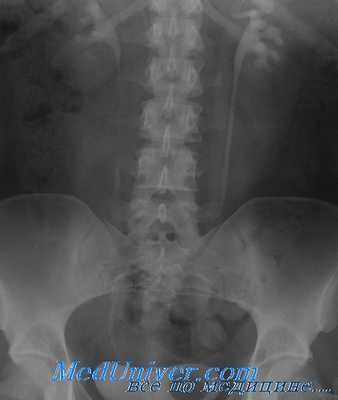

Кроме того на урограммах визуализируются поясничный отдел позвоночника, кости таза, тени почек.

Обзорная урография

С помощью обзорной урографии:

- оценивается внешний вид почек (их размер, положение, контуры);

- оцениваются рентгеноконтрастные тени, которые могут указывать на наличие конкрементов (камней).

Обзорная урография отличается отсутствием побочных эффектов. Исследование позволяет визуализировать средние и крупные конкременты (камни), но с его помощью не разглядеть мелкие детали.